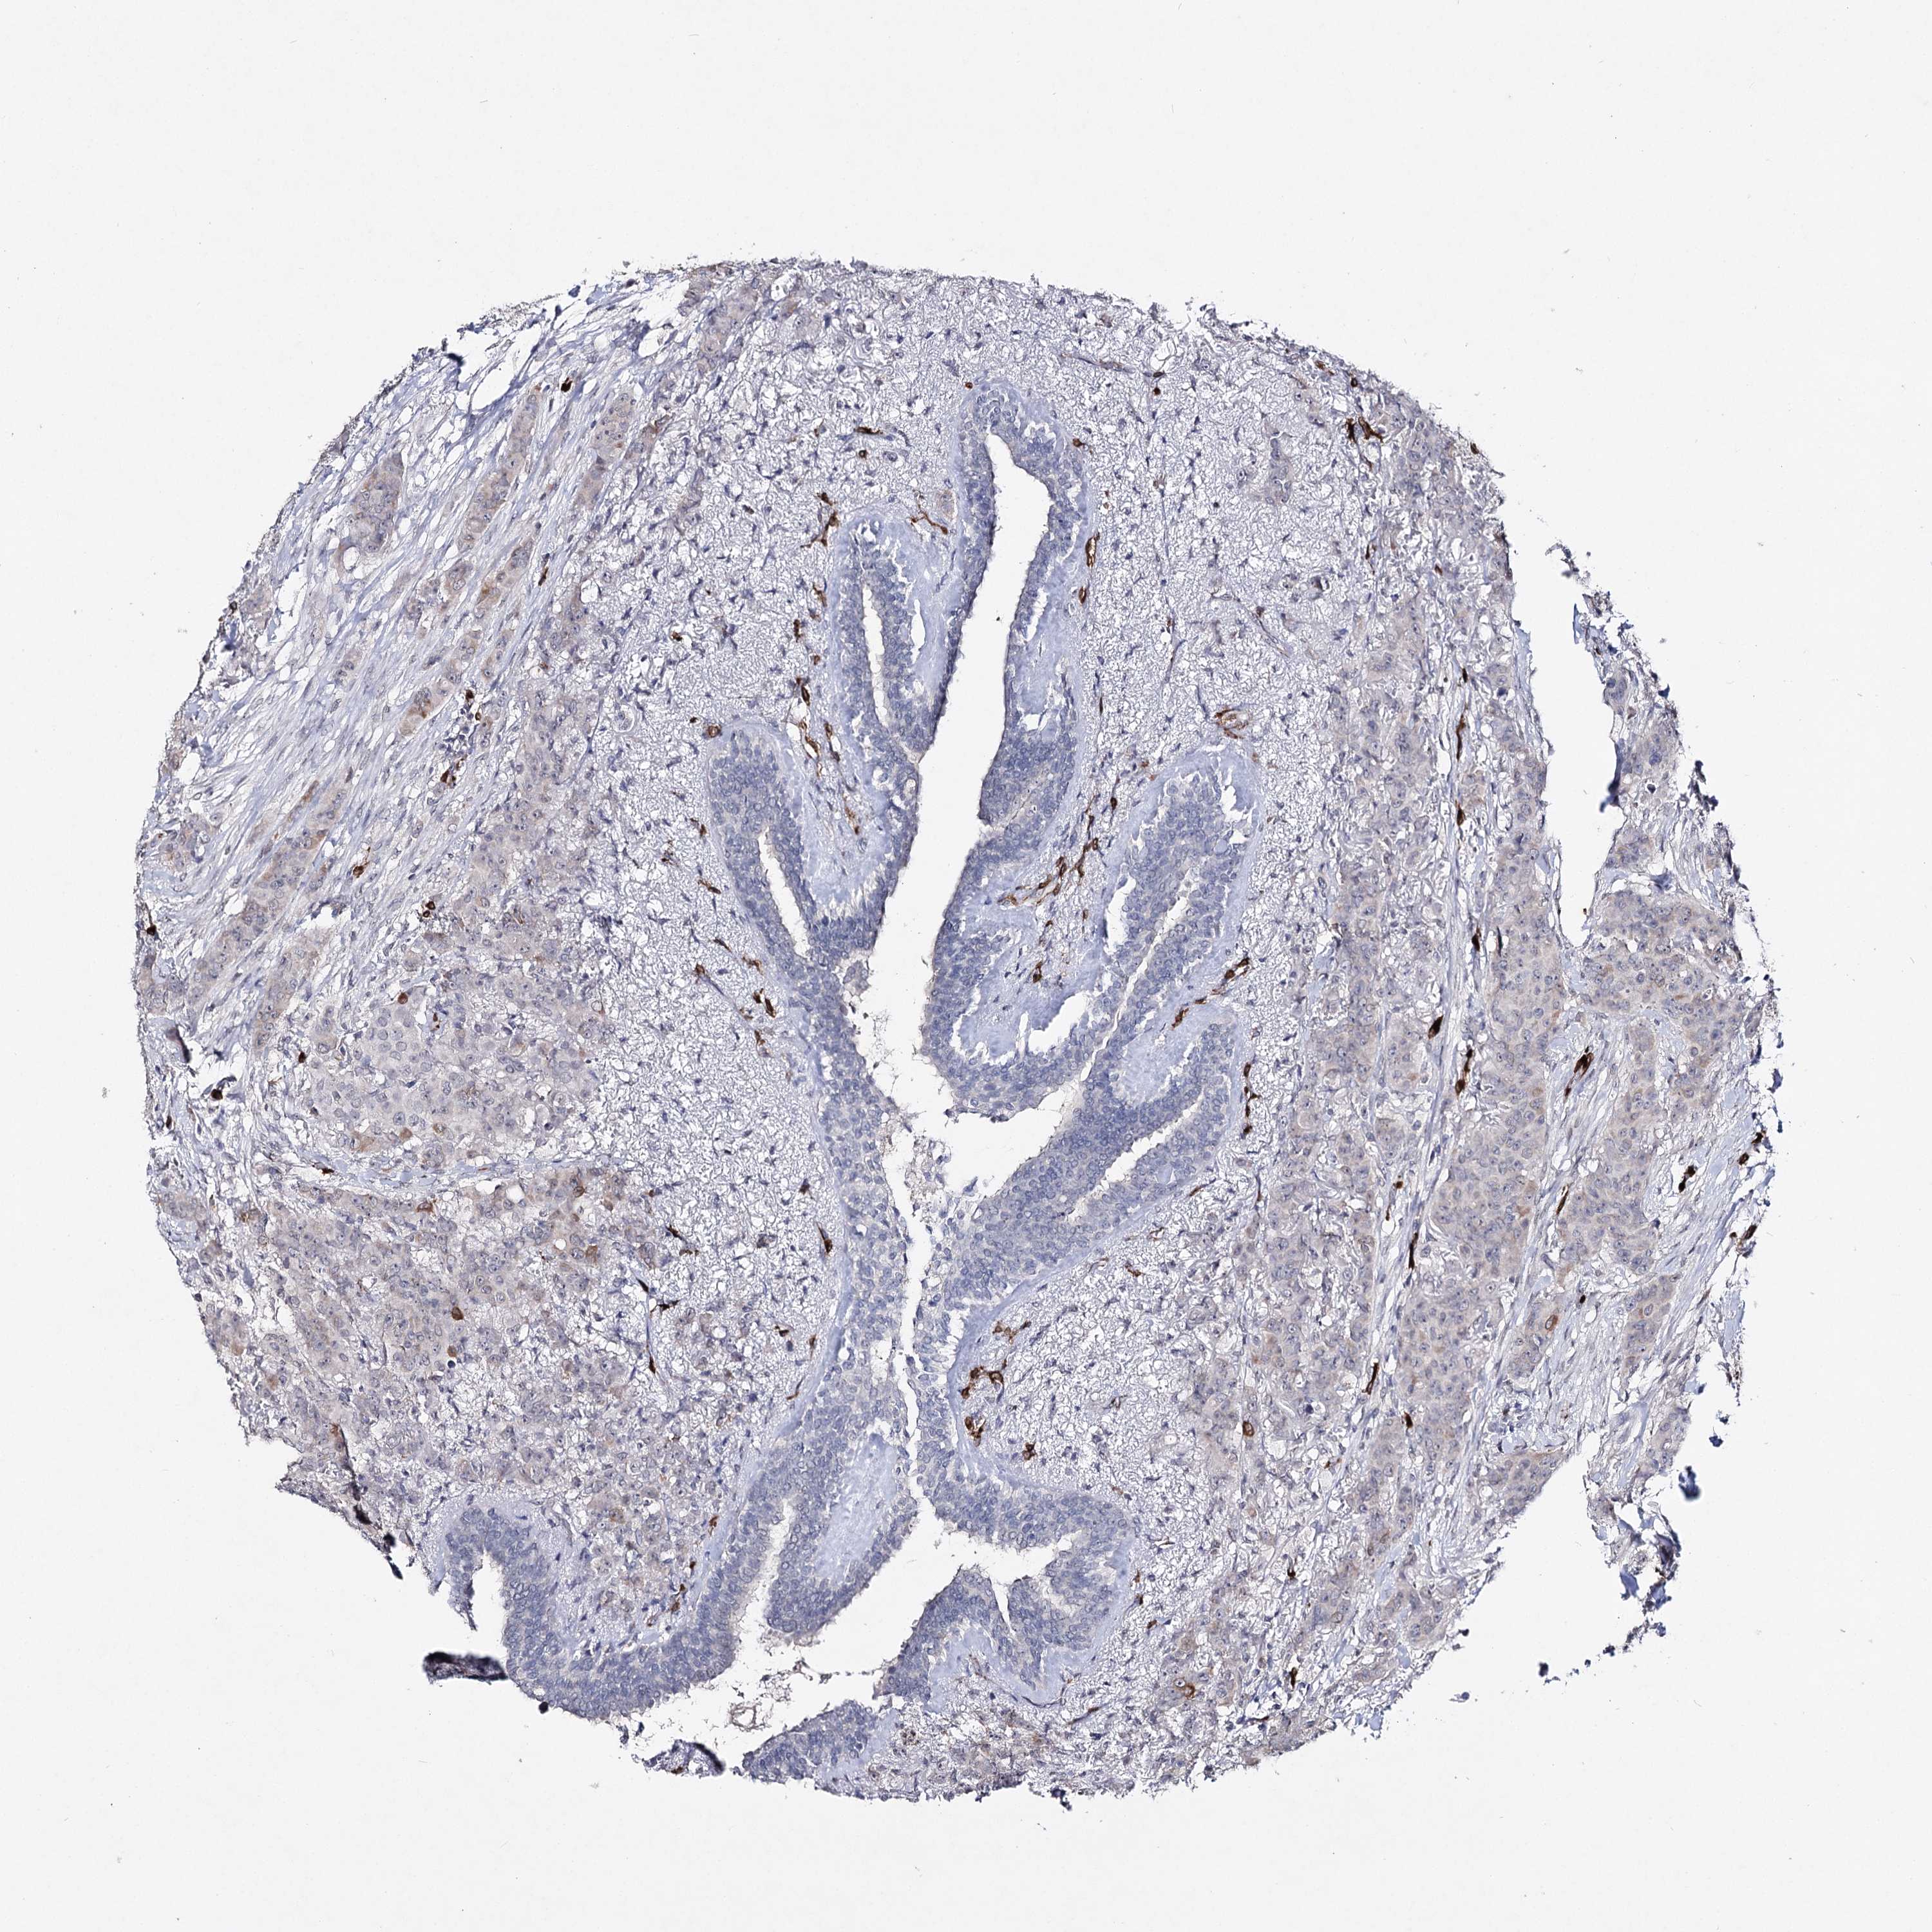

CANCER BREAST CANCER Show tissue menu

BRCA TCGA BRCA VALIDATION PROTEIN EXPRESSION